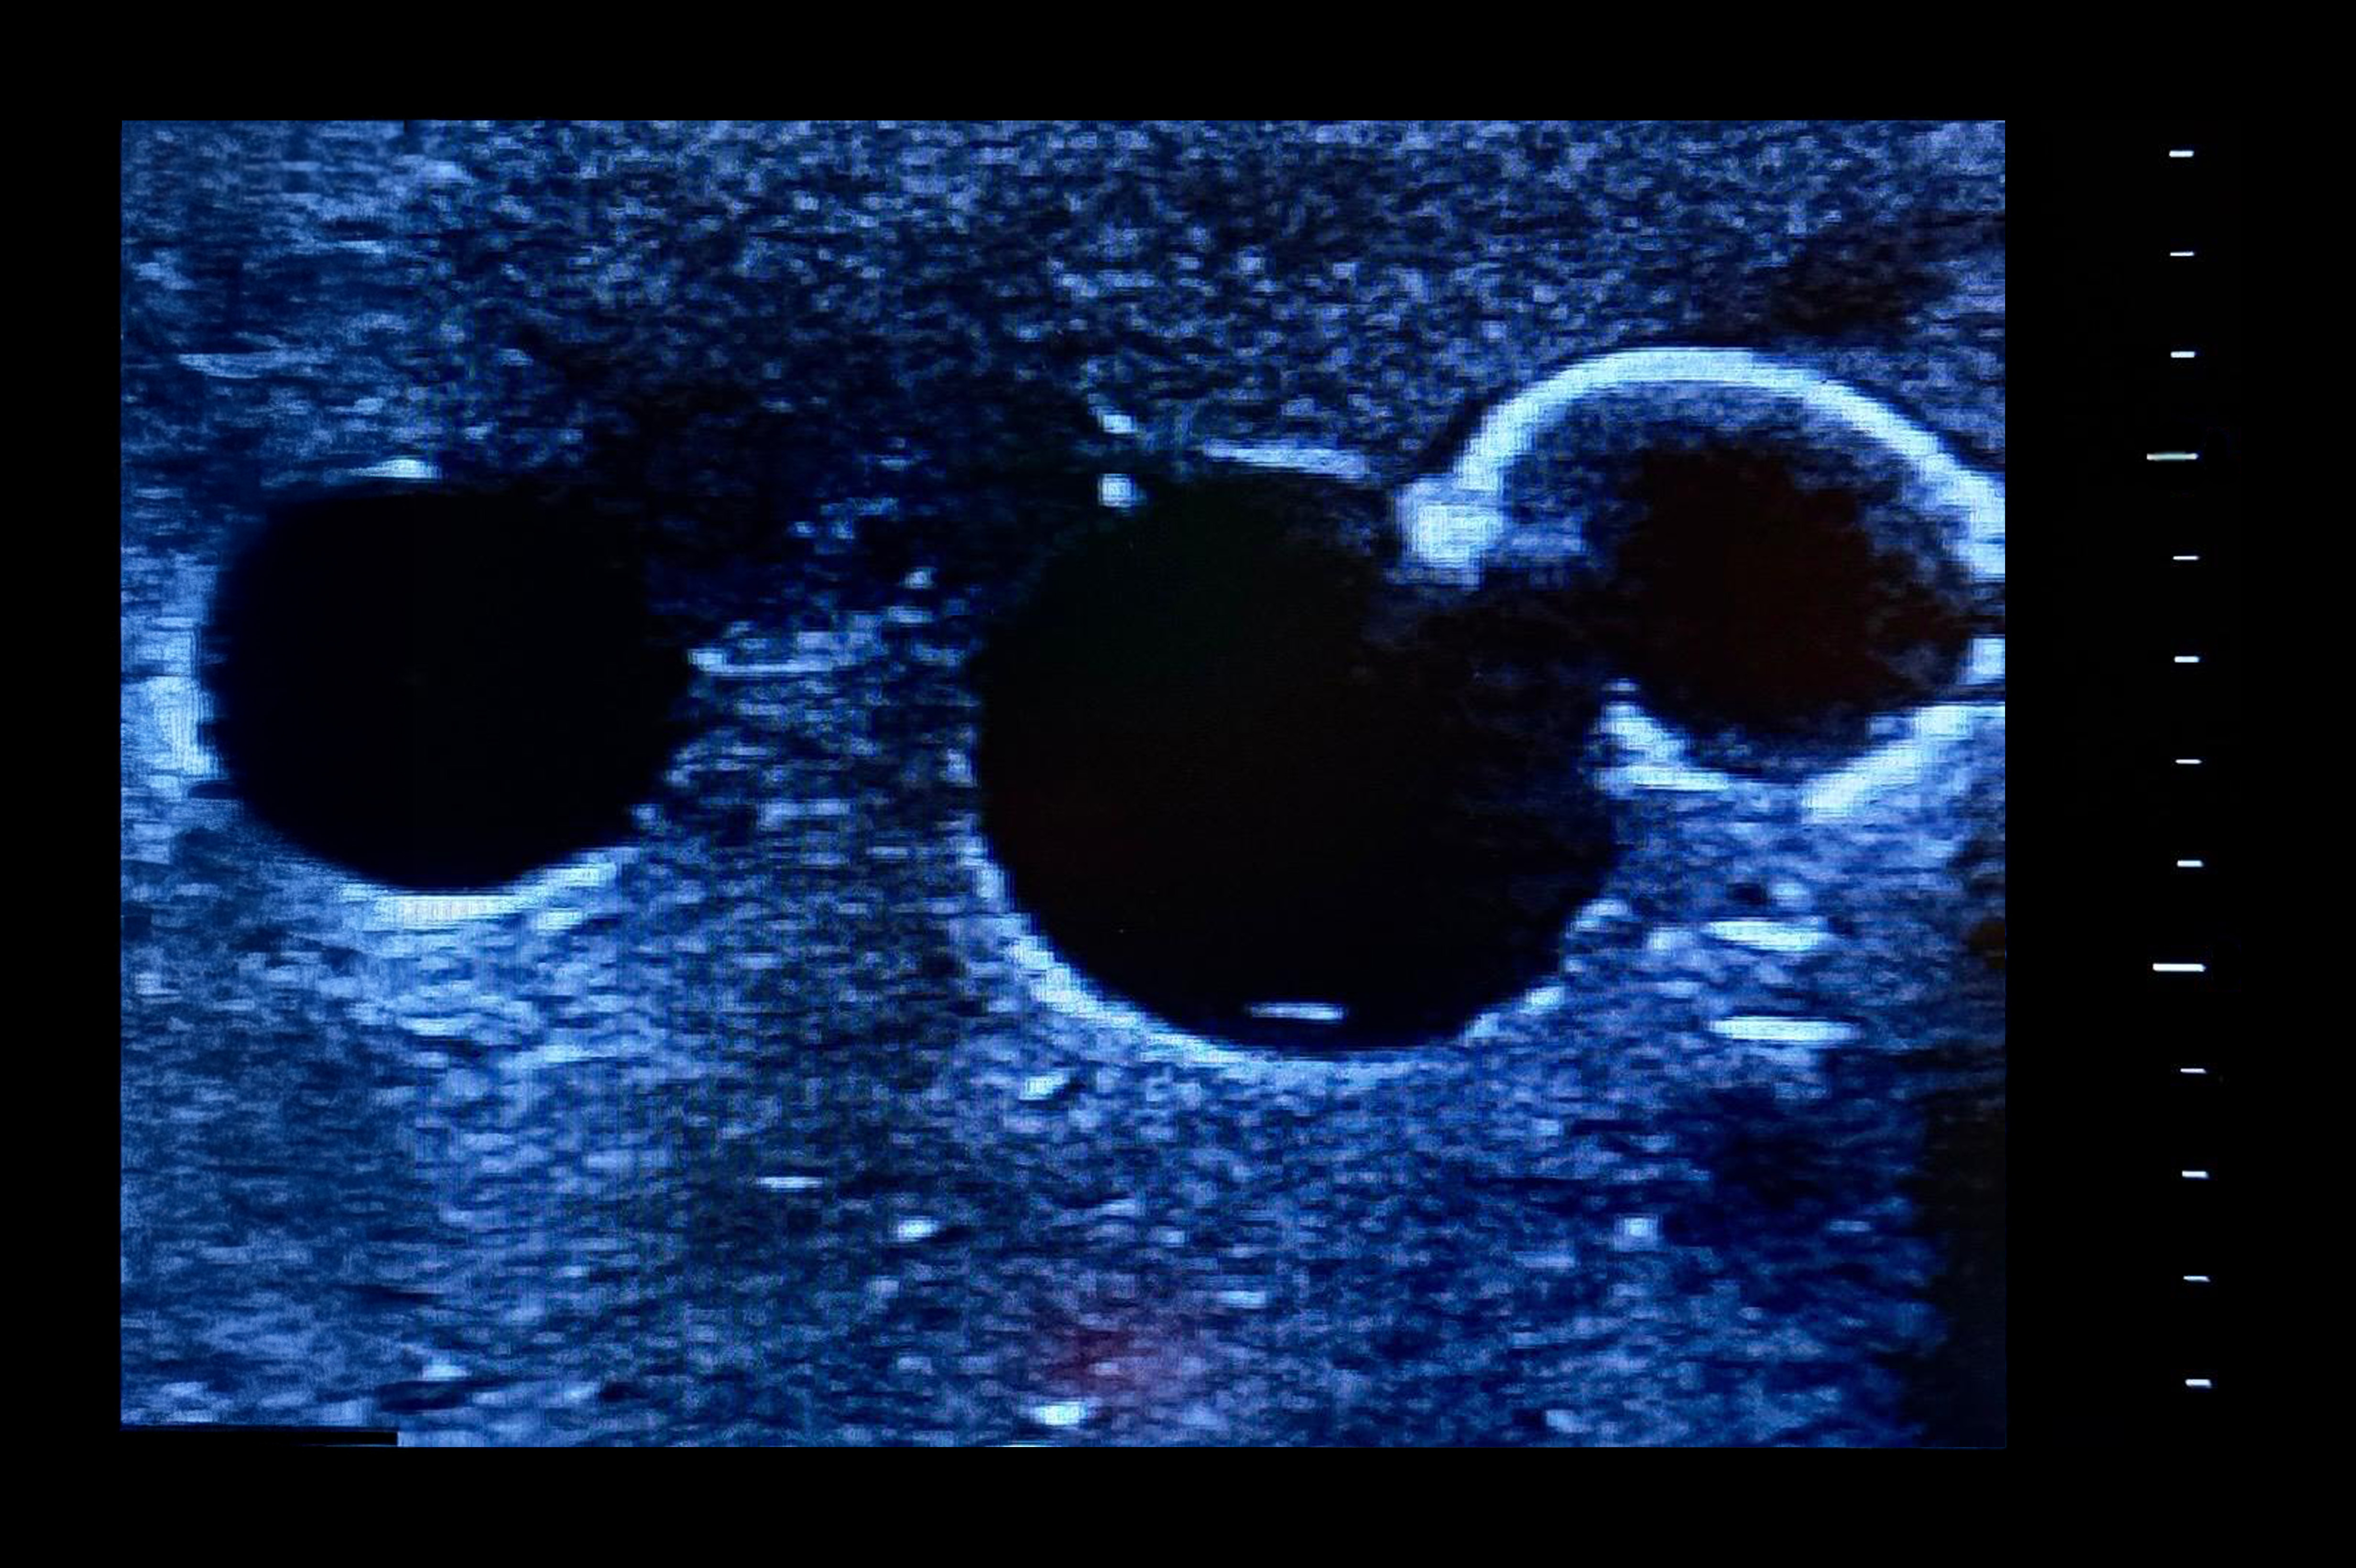

- Identification of veins under ultrasound

- Tubeless veins occlude when pressed either by hand or ultrasound probe

- Vein occlusion is visible under ultrasound